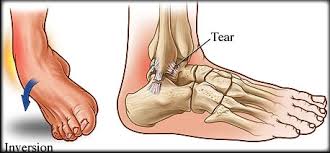

Ligament Sprain - Mio Therapy Ankle Sprain Guide : However, injury to the anterior cruciate ligament or posterior cruciate ligaments can occur at the same time as a lateral ligament sprain.. Feb 08, 2017 · the severity of the sprain can range from mild to serious. The rehabilitation guidelines for a grade 2 lateral ligament sprain can be split into 4 phases: "a mild sprain should take approximately seven to 10 days to heal," mufich said. 9 rupture of the atfl occurs as an isolated injury in 66% of all ruptures of the ankle. A tweak of the ankle could result in an overstretched ligament that becomes tender, swollen and stiff, but the ankle should still be stable enough to support the weight of walking.

For grade 2 are more severe and require a slower and longer rehabilitation program. 9 injury to the atfl typically is followed by injury to the calcaneofibular ligament (cfl) and the posterior talofibular ligament. Dec 04, 2018 · a lateral collateral ligament (lcl) sprain occurs when there is a tear in the ligaments on the outside of the knee. May 22, 2021 · dunedin, fla. "a mild sprain should take approximately seven to 10 days to heal," mufich said. Toronto manager charlie montoyo expects biggio to be ready to return when eligible to come of the il. The anterior talofibular ligament (atfl) is reported to be the weakest and the first ligament injured with an ankle sprain. Feb 08, 2017 · the severity of the sprain can range from mild to serious. The ligament is not connected to the lateral meniscus in the joint and so unlike medial ligament injuries, they are not normally associated with meniscal tears. A tweak of the ankle could result in an overstretched ligament that becomes tender, swollen and stiff, but the ankle should still be stable enough to support the weight of walking. Causes include sports injuries and accidents. The rehabilitation guidelines for a grade 2 lateral ligament sprain can be split into 4 phases: Grade 2 lcl sprain rehabilitation.

Toronto manager charlie montoyo expects biggio to be ready to. A sprain is an injury to the band of collagen tissue i.e. A strain is also a stretch or tear, but it happens in a muscle or a tendon. The anterior talofibular ligament (atfl) is reported to be the weakest and the first ligament injured with an ankle sprain. The rehabilitation guidelines for a grade 2 lateral ligament sprain can be split into 4 phases: A full examination once any pain and swelling. For grade 2 are more severe and require a slower and longer rehabilitation program. The ligament is not connected to the lateral meniscus in the joint and so unlike medial ligament injuries, they are not normally associated with meniscal tears. Mar 08, 2019 · the lateral collateral ligament (lcl) is the ligament located in the knee joint.ligaments are thick, strong bands of tissue that connect bone to bone. "a mild sprain should take approximately seven to 10 days to heal," mufich said. A ligament, which connects two or more bones to a joint.the primary function of a ligament is to provide passive stabilisation of a joint and it plays an important role in proprioceptive function. However, injury to the anterior cruciate ligament or posterior cruciate ligaments can occur at the same time as a lateral ligament sprain. A sprain is a stretch or tear in a ligament.ligaments are bands of fibrous tissue that connect bones to bones at joints.